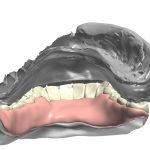

took off lower temps and scanned lower jaw. remaining teeth were used for long term temp abutments while implants healed. digital extractions performed and right vertical dimension for digital prosthesis design

Full arch imaging of mandible in preparation of overdenture